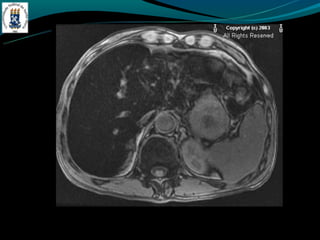

Peliose hepática